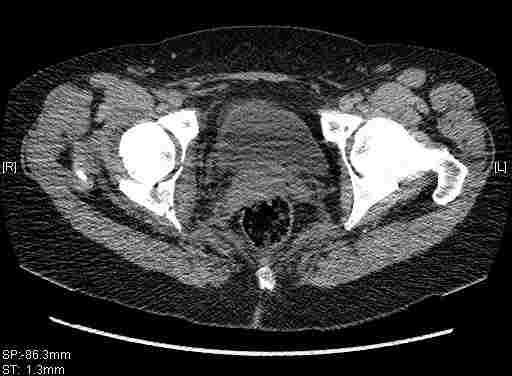

Удалось сегодня вывести пациентку в соседнюю больницу, где есть кт. Срезы сделаны только горизонтальные.